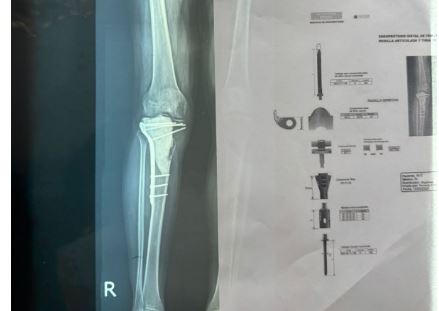

Los médicos ortopedas traumatólogos de los centros Trauma Care y Hospiten, realizaron durante el fin de semana una cirugía en el país, en la que extirparon un gran tumor de células gigantes con un comportamiento de malignidad de la tibia proximal.

Una vez realizada la intervención quirúrgica, donde extirparon el tumor de rodilla completa, colocaron al paciente una prótesis modular tumoral.

Explicaron, que la prótesis modular permite evitar la amputación, preservando la función de la extremidad, que a su vez puede mejorar la movilidad y la calidad de vida del paciente, permitiéndole realizar actividades diarias.

“Se colocó una prótesis modular tumoral que alberga una fijación a nivel del fémur, una bisagra que va a ser a su vez de rodilla y una implementación de varios módulos para conformar lo que es la tibia y una fijación intramedular, luego se hizo una reconstrucción, el paciente se encuentra en buenas condiciones de salud y este es un procedimiento que permite que el paciente conserve su miembro que tenga la funcionalidad de la prótesis y le permita realizar sus actividades tanto física como laborales y deportivas, que es la finalidad de los médicos, devolverle sus funcionalidades al paciente”, puntualizó.